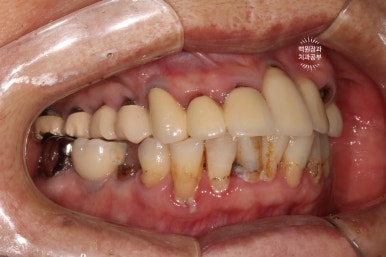

좌측은 위턱 사진, 오른쪽은 아래턱 구강내 사진입니다.

아주 어렵지 않게 두 치아가 부러져 있다는 것을 확인할 수 있죠.

왼쪽 측면과,